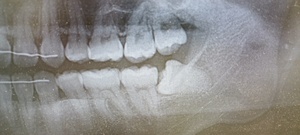

どうやって診断される?|検査・受診の流れを解説

歯科・口腔外科での診察方法

医師の視診で典型的な白斑や網目状の模様が観察されれば、口腔扁平苔癬と仮診断されることが多いです。

組織検査(生検)が必要なケースとは?

-

白斑が厚く、患部が硬い、出血しやすい

痛みが強く、潰瘍がある

がん化のリスクを排除したい場合

このような場合には粘膜の一部を採取する生体検査(生検)が行われます。